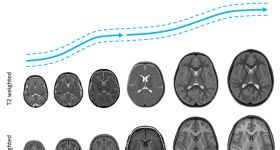

帕金森病PD的臨床過程中使用的診斷和進(jìn)展影像學(xué)生物標(biāo)志物的時(shí)間相關(guān)性。對磁共振成像T1加權(quán)成像/單光子發(fā)...

最近,神經(jīng)影像學(xué)研究的一個(gè)重點(diǎn)在于研究產(chǎn)前、新生兒和兒童早期的大腦發(fā)育。發(fā)育早期腦損傷和早產(chǎn)情況與兒童...